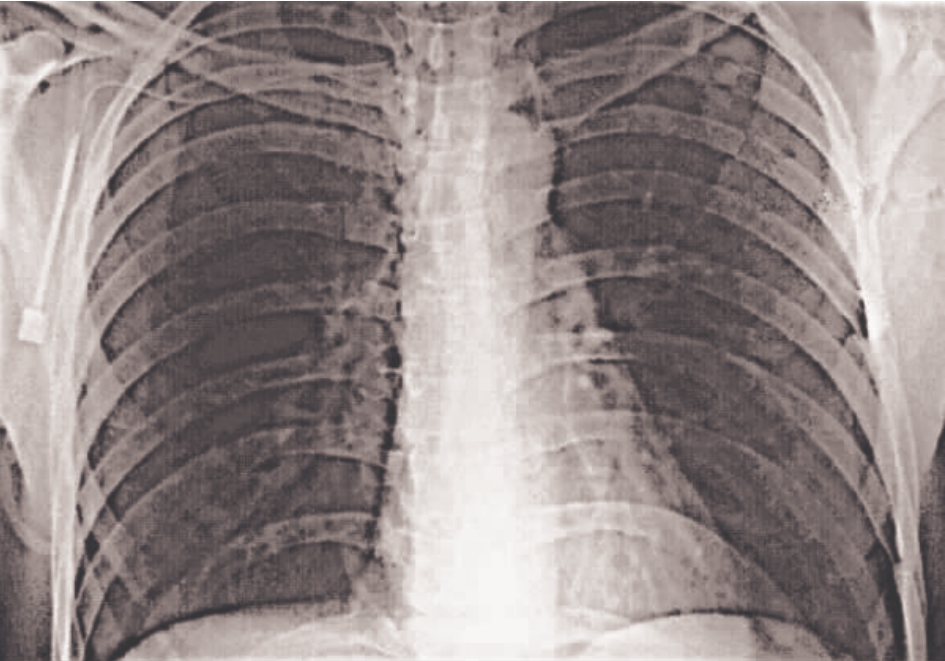

和低通滤波器相反,高通滤波器通过削弱傅里叶变换的低频而保持高频相对不变,会使图像变得更加清晰(锐化)。通常给高通滤波器加上一个偏移量,构成高频强调滤波,再和直方图均衡化结合起来使用,所得到的结果要好于单独使用任何一种方法所得到的结果。在work目录下,调用lpfilter.p、hpfilter.p和gscale.p函数可以实现高频强调滤波的效果。图2-53是一幅数字胸部X射线原图像,图2-54是高通滤波后的图像,模糊地显示出原图像的主要边缘。图2-55是高频强调滤波后的结果,低频部分成分引起的灰度级色调得以保持。图2-56是对高频强调滤波处理的结果,用直方图均衡化后的图像,可以清楚地看到骨骼结构。程序代码如下:

img59

图2-54